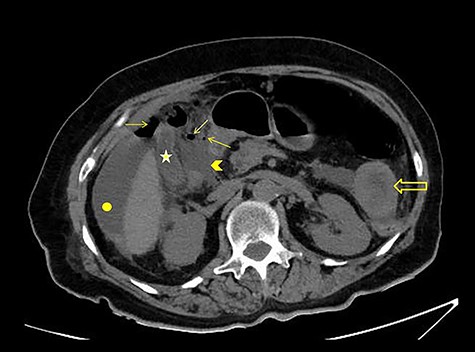

CT scan without intravenous (iv) and oral (per os) contrast media administration: The disruption of lumen continuity at the level of duodenum bulb with presence of fluid (arrow head) and free air (arrows). There are also presence of free fluid in subdiaphragmatic space (dot) and edema in jejunum wall (open arrow). Contracted gallbladder is noted by star.